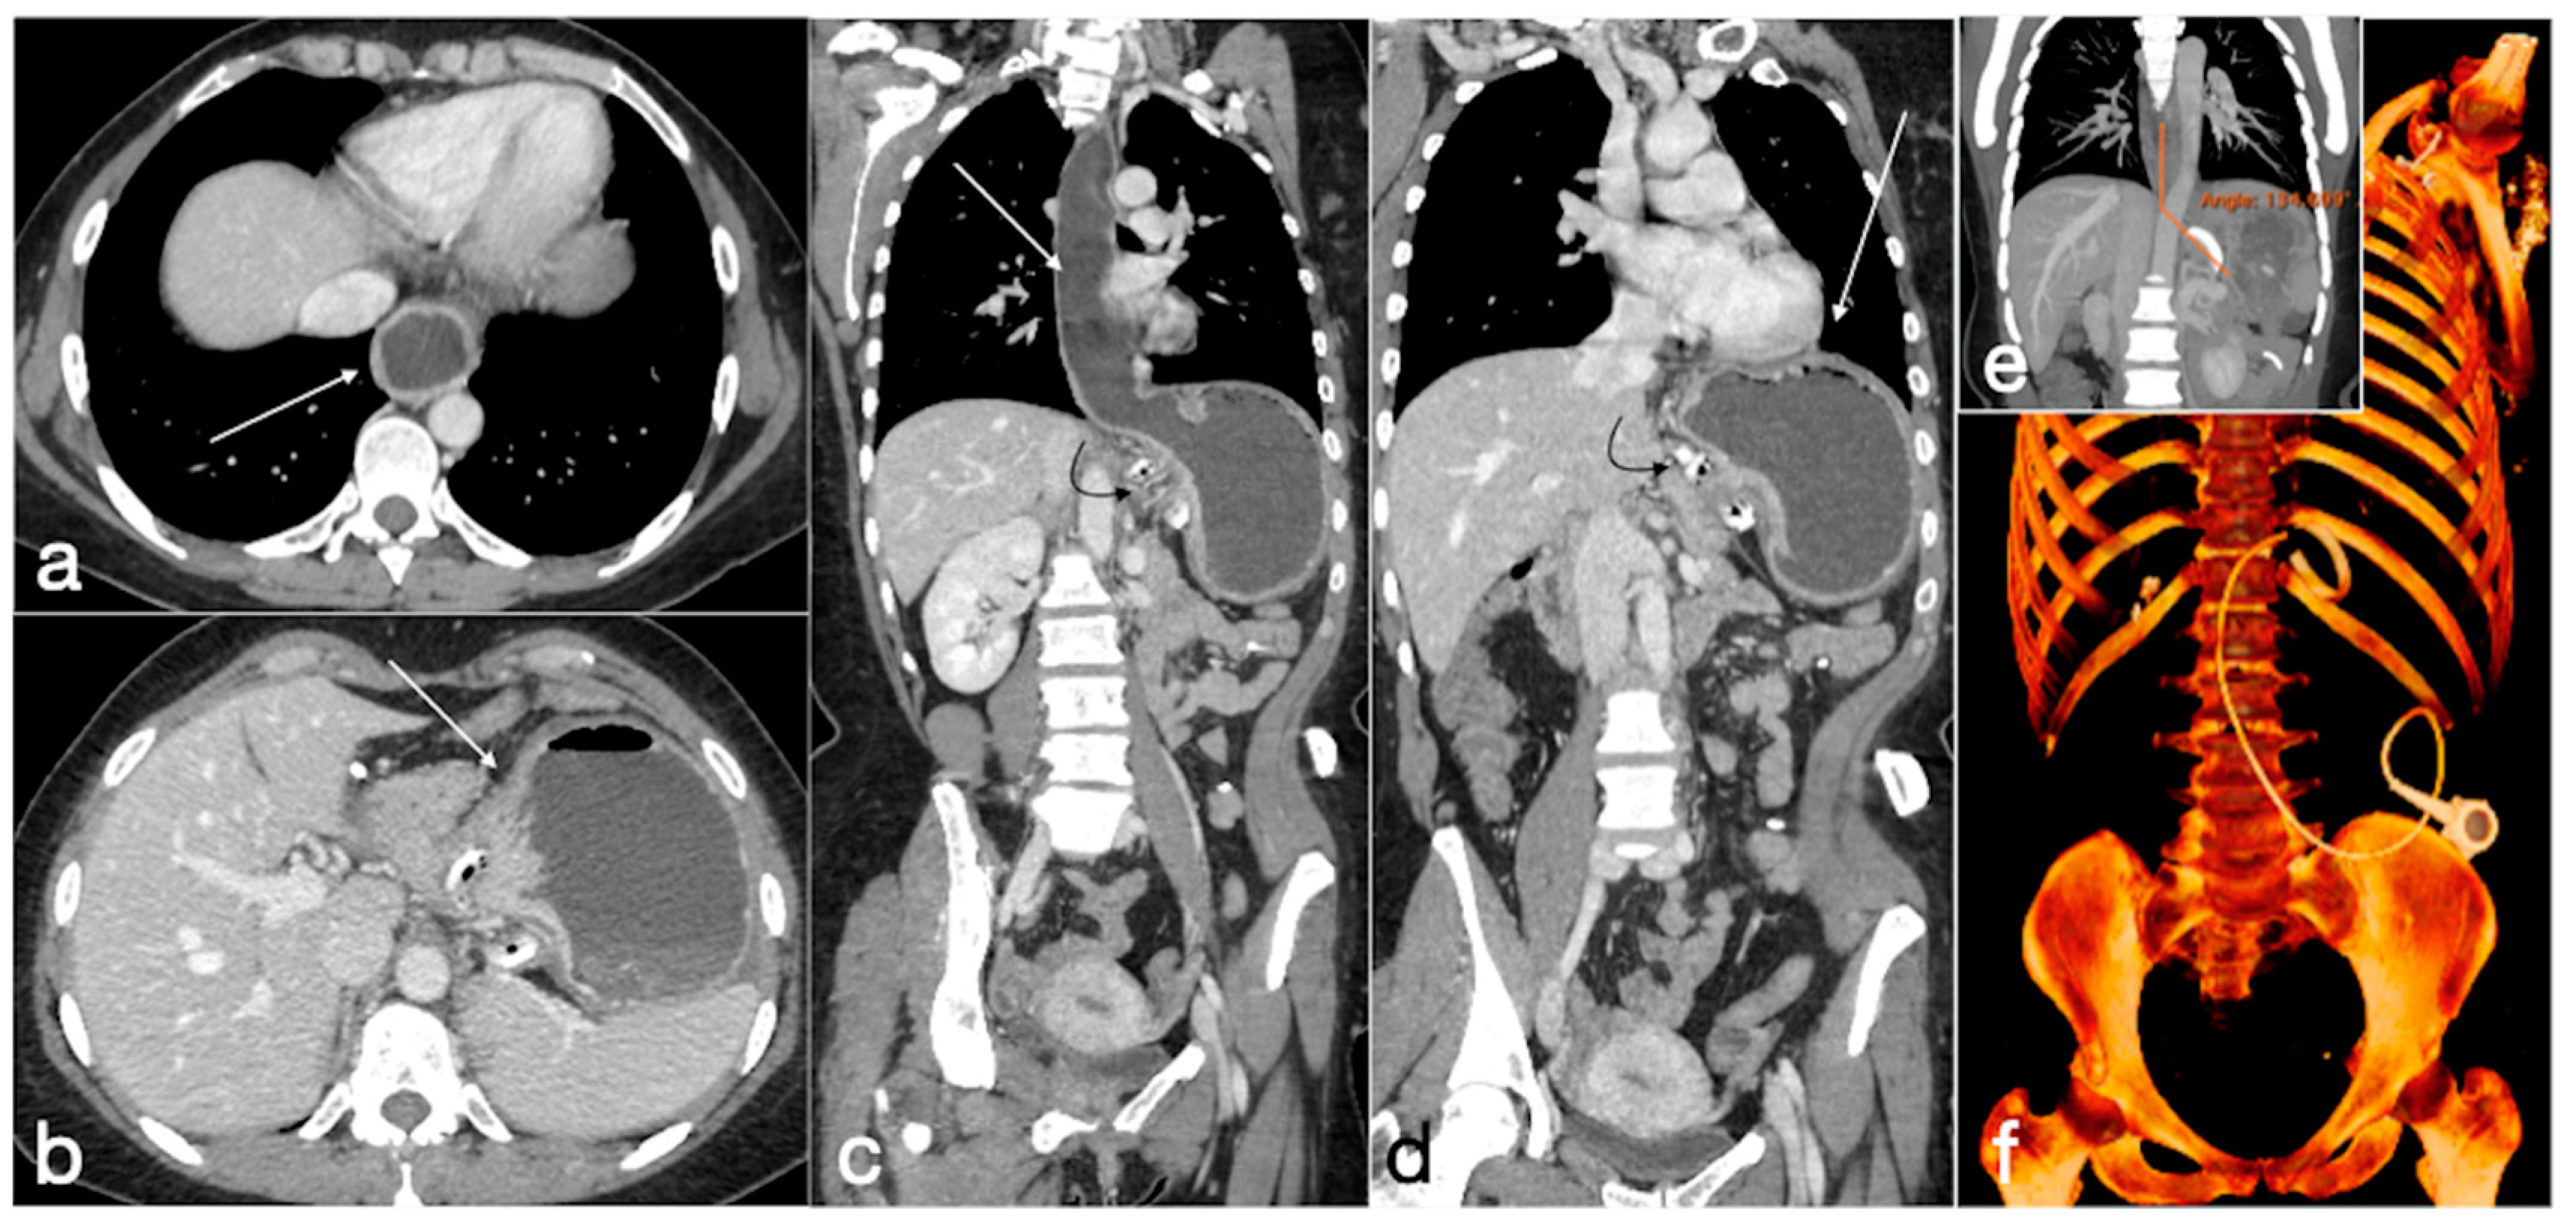

3.4. Unexpected Complication